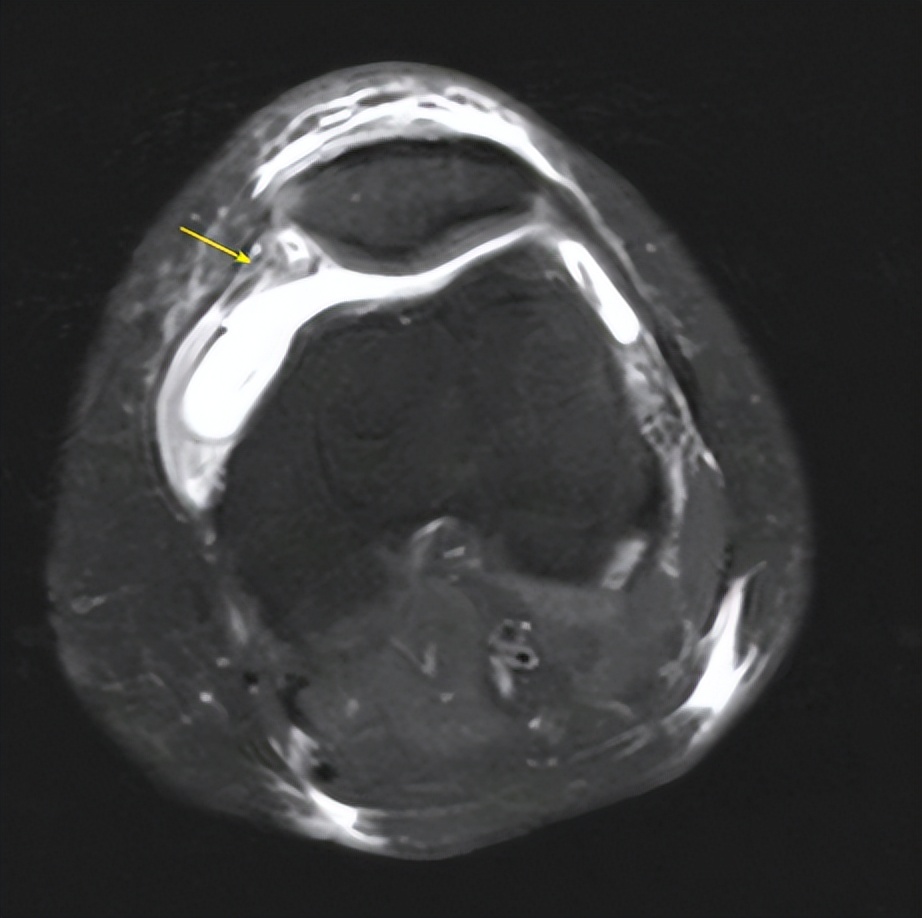

△术前脱位的髌骨(左图),髌股韧带重建后髌骨恢复正常位置(右图)

1

2

△术前可见髌股韧带断裂(左图),术后可见重建的韧带(右图)